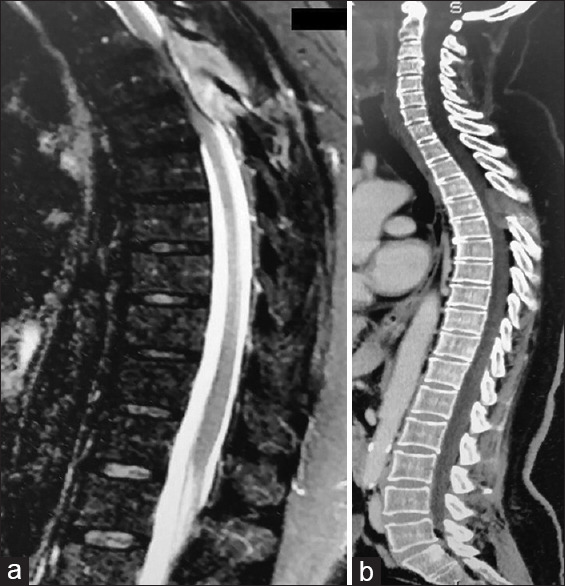

Abstract Image